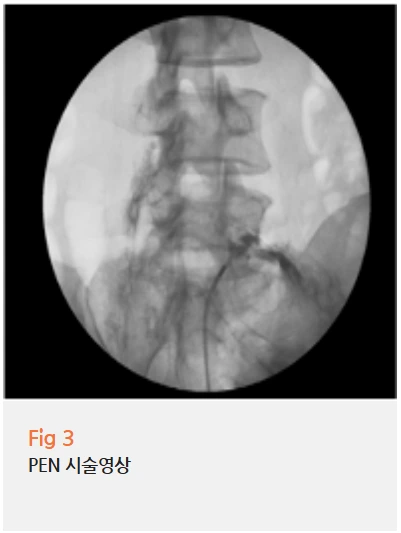

✔️ 허리 전방전위증으로 인한 협착 → PEN 시술

PEN 시술은 'Percutaneous Epidural Neuroplasty'의 약자로,

가느다란 특수 카테터를 신경 주변까지 정확하게 삽입해서

유착된 조직을 풀어주고 약물을 직접 주입하는 시술이에요.

기존의 일반 주사 치료는 신경 주변까지 정확히 도달하지 못하는 경우가 많은데,

PEN 시술은 C-arm(영상투시장치)을 보면서 실시간으로 위치를 확인하기 때문에

눌린 신경 부위를 정확하게 타겟팅할 수 있습니다.

이 환자분의 경우, 요추 4-5번, 5번-천추1번 두 군데에 신경협착이 있었기 때문에

PEN 시술로 정확하게 약물을 전달하는 것이 핵심이었어요.